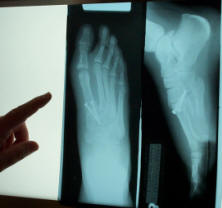

the first of four surgeries to correct Kathryn's feet. |

One of the many trips to the doctor for Kathryn to

have stitches removed, casts changed, x-rays... and to deliver

cookies and treats to the surgeons the LORD

used to change her life! |

On wheels again, another surgery...and barbecues! |